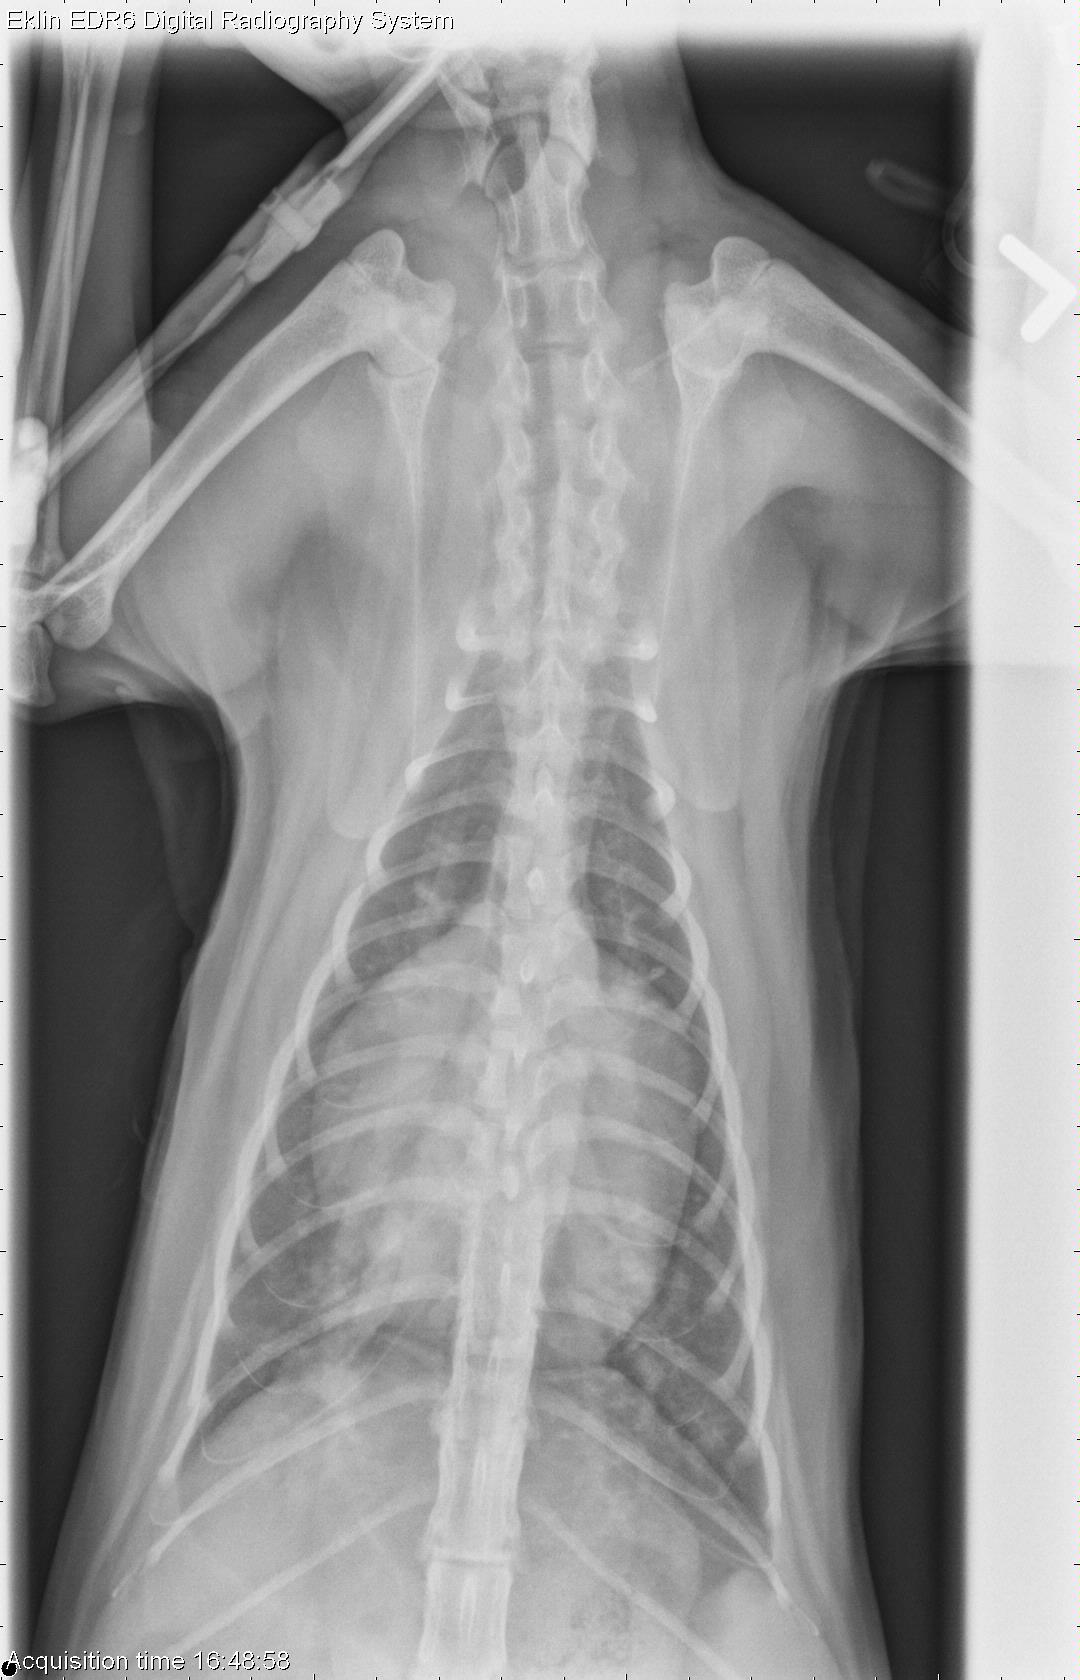

This week’s case is a 1-year-old male neutered Domestic Shorthair with respiratory distress and PCV of 10%. What are your differential diagnoses?

DV Thorax

The cardiac silhouette is markedly enlarged and rounded. The pulmonary vasculature is enlarged and there is a bronchointerstitial pattern in the caudal lung lobes. The remainder of the thoracic structures appear normal.

• Cardiomegaly (dilated cardiomyopathy, volume distension)

• Pulmonary edema secondary to heart failure

Cardiac dilation secondary to increased cardiac volume with high volume heart failure. Possible early DCM. Myelofibrosis was found as the reason for the severe anemia and pancytopenia.